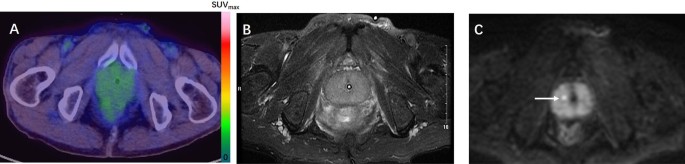

As shown in Table 2, among the 33 patients with confirmed PCa, 28 were positive on mpMRI and five were negative. 68Ga-PSMA-617 PET/CT showed that 29 patients were positive and four were negative. Of the 34 patients with benign diagnoses, 16 were positive on mpMRI and 18 were negative. 68Ga-PSMA-617 PET/CT showed that four patients were positive and 30 were negative. The patient-based sensitivity, specificity, PPV, and NPV of 68Ga-PSMA-617 PET/CT were 87.88% (29/33, 95% CI 80.86–96.04%), 88.24% (30/34, 95% CI 71.61–96.16%), 87.88% (29/33, 95% CI 70.86–96.04), and 88.24% (30/34, 95% CI 71.61–96.16%) respectively. The corresponding values for mpMRI were 84.85% (28/33, 95% CI 67.33–94.28), 52.94% (18/34, 95% CI 35.40–69.84), 63.64% (28/44, 95% Cl 47.74–77.17%), and 78.26% (18/23, 95% CI 55.79–91.71%) (Table 3). We performed an ROC analysis for the two examinations and compared the results at a patient-level (Fig. 2). The AUC values of 68Ga-PSMA-617 PET/CT and mpMRI were 0.881 (95% CI 0.778–0.947) and 0.689 (95% CI 0.564–0.796) respectively, which indicated that 68Ga-PSMA-617 PET/CT may have a better diagnostic performance (P = 0.0019). SI Figure S1 shows a representative case in which the primary lesion could be detected by both 68Ga-PSMA-617 PET/CT and mpMRI. Figure 3 shows a representative case in which 68Ga-PSMA-617 PET/CT could correct false-positive errors of mpMRI with superior specificity.

A 73-year-old patient with a PSA level of 4.29 ng/ml. The biopsy results of the two punctures showed chronic granulomatous inflammation of the prostate tissue. After 3 months of follow-up, the PSA fluctuations ranged from 3.52 to 5.39 ng/ml, suggesting benign lesions. 68Ga-PSMA-617 PET/CT (A) showed no significant change in the uptake of 68Ga-PSMA-617 in the prostate, with an SUVmax of 3.0, consistent with benign prostatic lesions. In mpMRI, there was no obvious abnormal signal on T2W (B), but DWI (C) suggested indicated a spot abnormal signal in the center of the right side of the prostate (indicated by the arrow), suggesting PCa, but it was inconsistent with the pathological results.